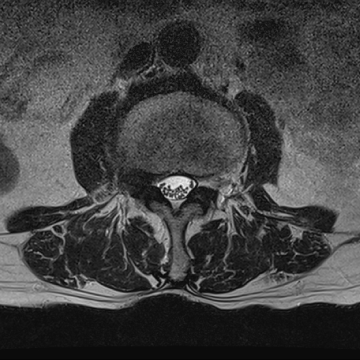

허리 디스크 수술 전·후

2022.09.05

2022.09.08